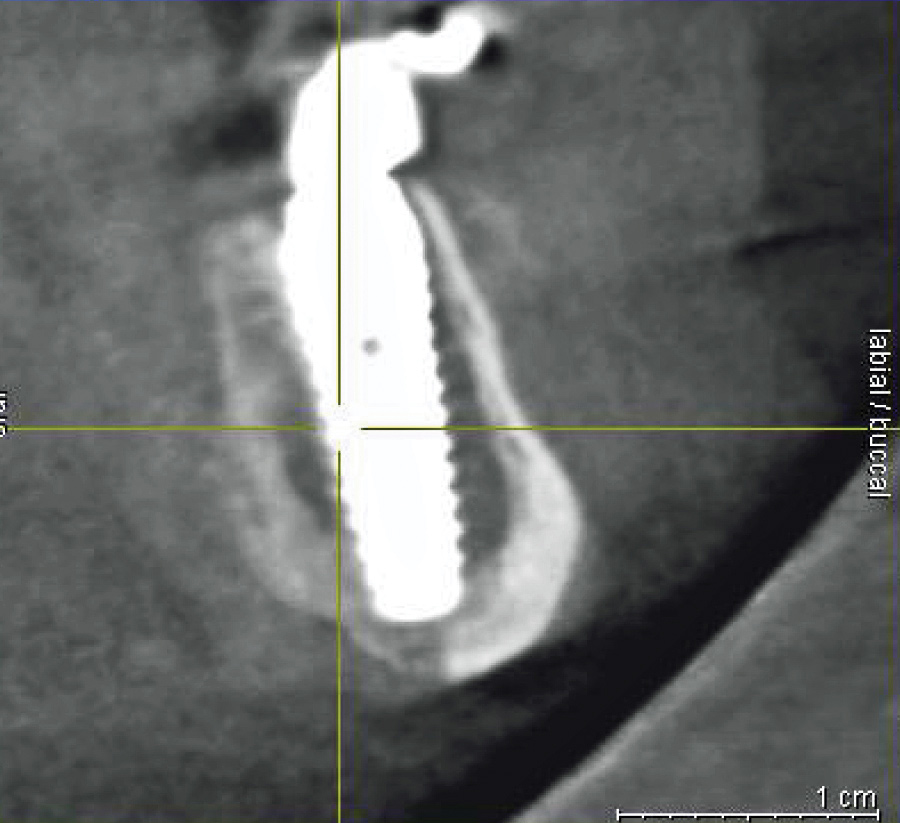

Fig 3. Presurgical cross-sectional CBCT scan slice of an All-on-4–style dental implant patient with crestal location of the inferior alveolar nerve (yellow crosshairs on nerve) secondary to bone resorption. Bone reduction in this location risks exposure and damage to the nerve.

In cases of severe mandibular atrophy, supracrestal exposure of the mental foramen or inferior alveolar nerve (Figure 3) may be possible.8,22 When encountered, these situations require special consideration for incision design, mucogingival flap reflection, bone reduction, dental implant placement, soft-tissue reduction, and suturing. With exposed nerve tissue, each of these steps has the potential for causing damage.

When faced with an exposed inferior alveolar nerve, the author has placed dehydrated human amnion-chorion membrane (DHACM) directly onto the nerve fibers based on the positive outcomes that have been reported with DHACM nerve wraps around the prostatic neurovascular bundle in prostatectomy surgeries.23 In 4 cases of DHACM that the author used inferior alveolar nerve wraps, patients reported no adverse outcomes, such as permanent or transient anesthesia, paresthesia, hypoesthesia, or dysesthesia.